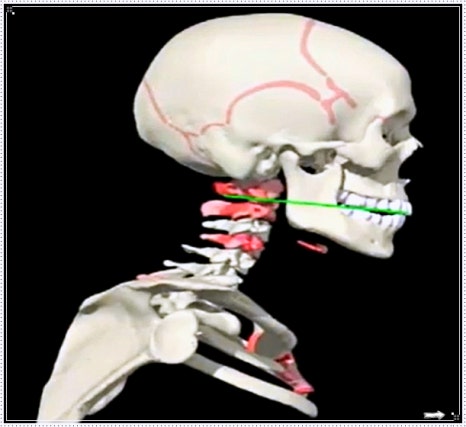

하지만 턱관절의 상태는 자세와 매우 깊은 관련이 있습니다.

목이 앞으로 나오는 거북목 자세

스마트폰을 오래 보는 습관

한쪽으로 기운 어깨나 턱선

이런 것들은 모두 턱의 균형을 깨뜨릴 수 있습니다.

몸은 하나로 연결되어 있기 때문이죠.

어깨가 틀어지면 목 근육이 당기고, 그 긴장감이 결국 턱 주변으로 이어집니다.

그래서 부산턱관절한의원에서는 턱 부위만 보는 것이 아니라 전신의 균형과 근육 긴장도까지 함께 살핍니다.

특히 턱관절 추나 교정은 단순히 턱만 맞추는 게 아니라 머리·목·어깨·턱의 정렬을 함께 바로잡는 과정입니다.

자세가 바로 서면 턱의 부담이 줄어들고, 소리나 통증이 완화되는 경우도 많습니다.